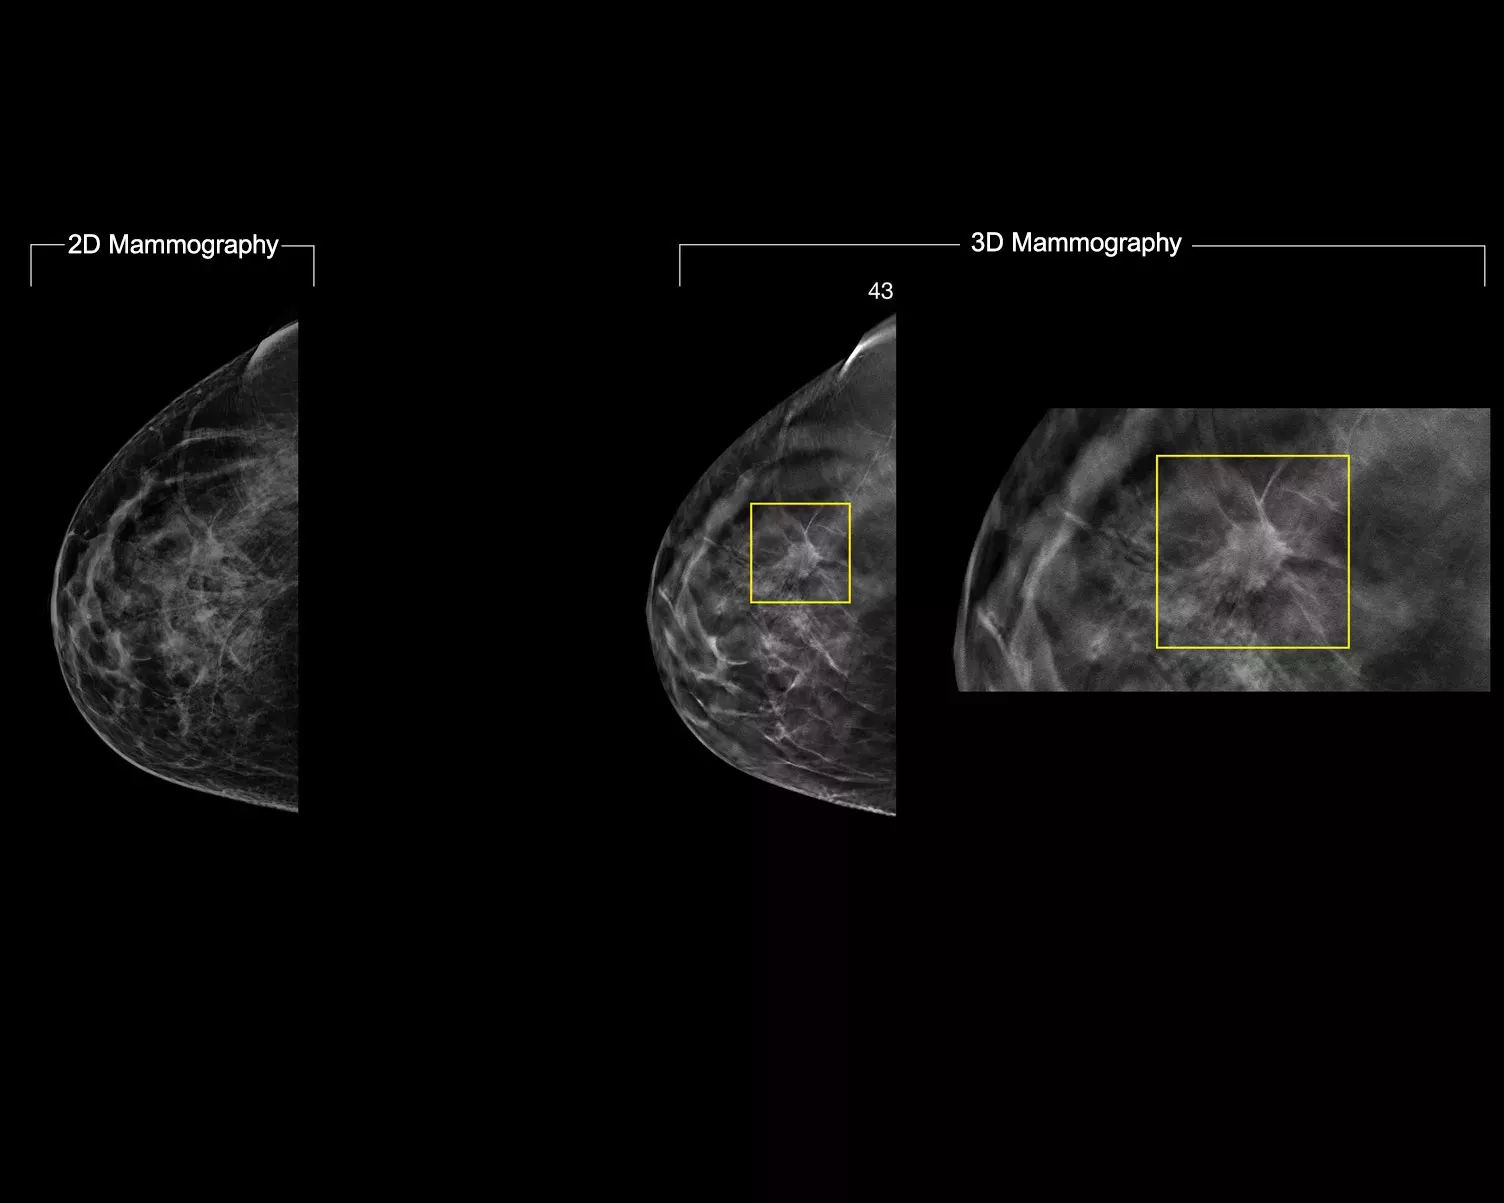

A deep-learning algorithm designed to aid radiologists' diagnostic performance and detect breast cancer1-3 from tomosynthesis images obtained using the Hologic Dimensions Mammography® Systems. The algorithm locates lesions that are likely to represent breast cancer by searching each slice of the tomosynthesis image set. The suspicious areas are highlighted for concurrent reading at the radiologist's workstation to aid in interpretation.

Study shows +9% improvement in observed reader sensitivity for cancer cases.1.2 Works on standard and high-resolution tomosynthesis images; overlay on 3DQuorum SmartSlices and synthesised 2D images.

Tools for Easy Lesion Identification

The algorithm looks for 3 main groups of suspicious lesions: calcifications, masses, densities and distortions, and any combination of these lesions. Outputs may vary on different reading workstations.